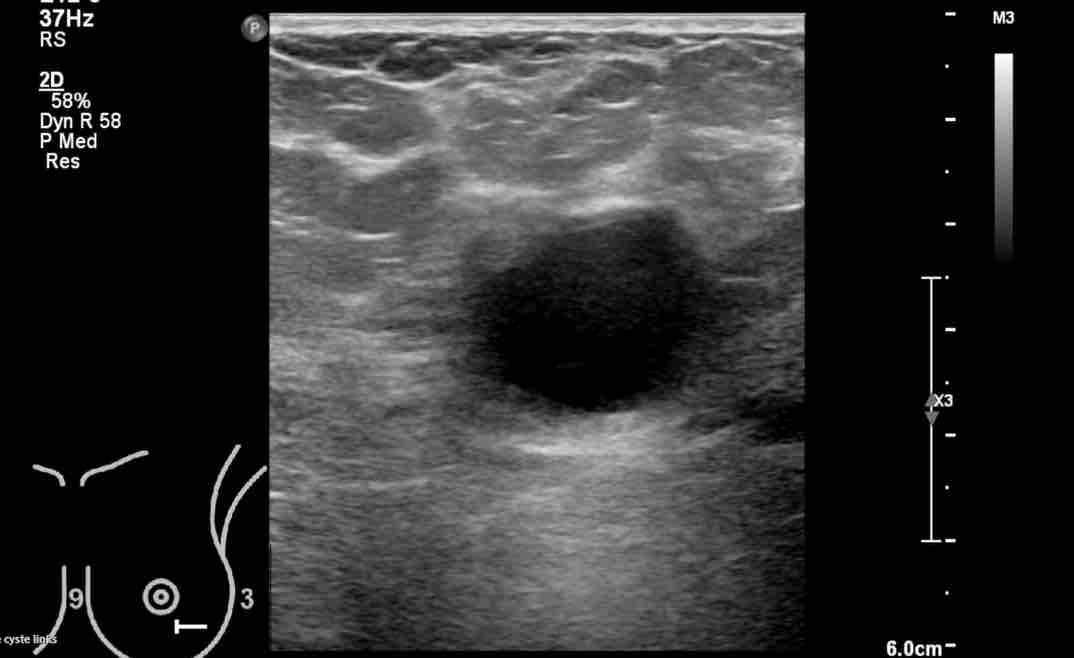

Nang là loại khối u lành tính phổ biến nhất ở vú.

Đây là các túi chứa dịch nằm bên trong tuyến vú và luôn luôn có bản chất lành tính.

Việc xác định bản chất dạng nang của một khối u có thể sờ thấy là vô cùng quan trọng, vì khi đó bác sĩ có thể hoàn toàn yên tâm trấn an bệnh nhân rằng mọi thứ đều ổn.

Trên siêu âm, các đặc điểm điển hình của nang bao gồm:

- Hình ảnh trống âm (hay còn gọi là vùng đen)

- Hình dạng tròn hoặc bầu dục

- Bờ rõ nét, giới hạn rõ ràng

- Tăng âm phía sau

Phía sau nang thường có hiện tượng tăng âm, còn gọi là tăng âm phía sau, đề cập đến sự gia tăng các tín hiệu âm ở phía sâu sau nang, do dịch lỏng truyền âm rất tốt.

Khi dịch trong nang chịu áp lực căng, nang trở nên tròn hơn và có thể sờ thấy được.

Đây là một ví dụ điển hình về nhiều nang ở một phụ nữ có khối u sờ thấy được ở vú.

Mặc dù có nhiều nang, nhưng chỉ có nang ở trung tâm mới sờ thấy được, vì nang này có hình tròn với dịch chịu áp lực căng bên trong.